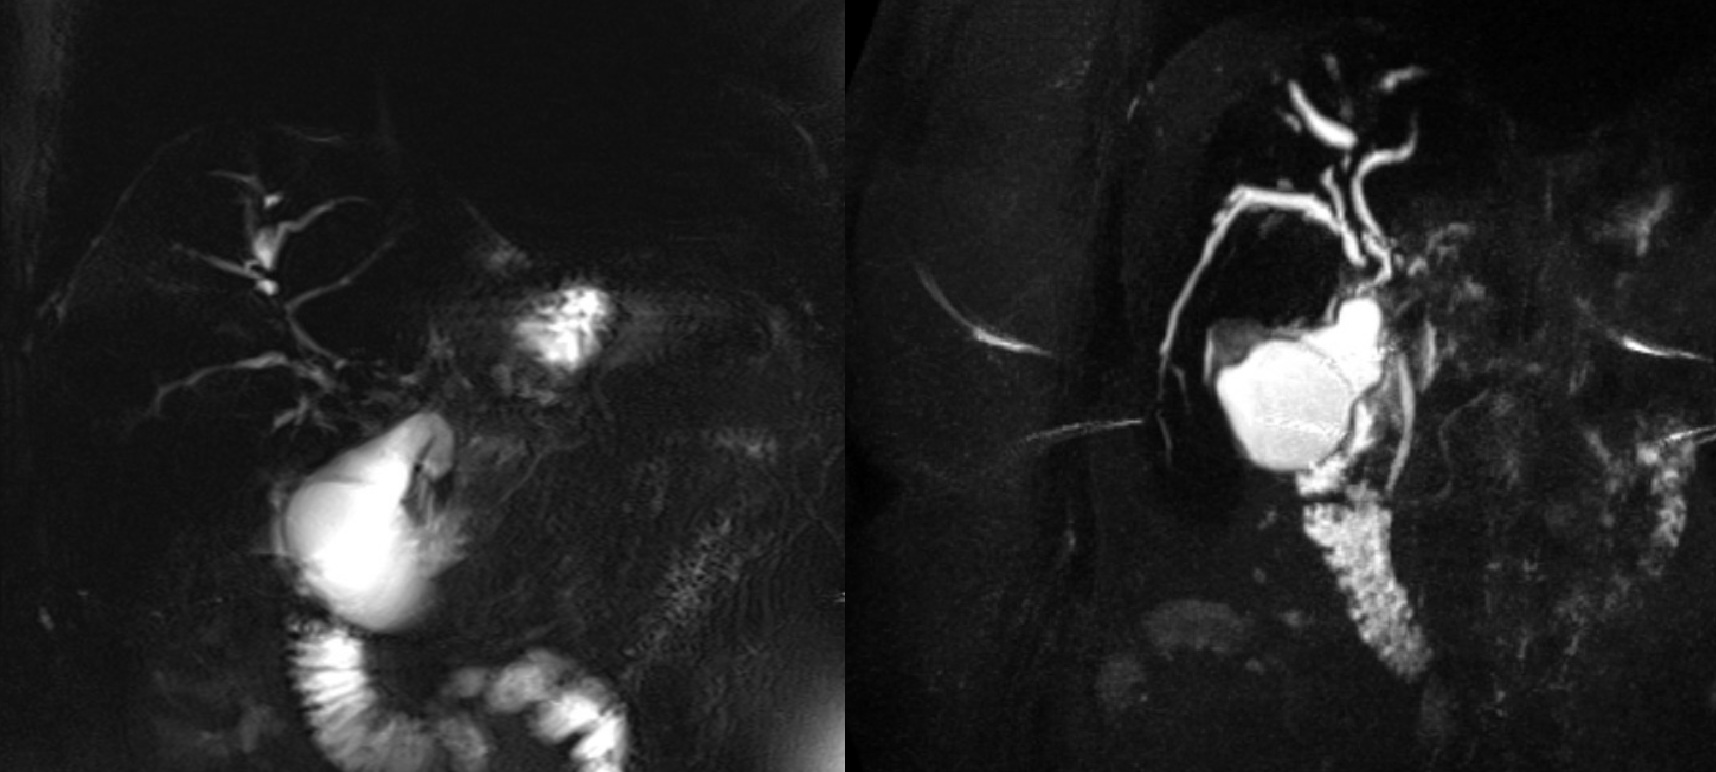

Magnetic resonance cholangiopancreatography (MRCP) images of a patient with primary sclerosing cholangitis (PSC), captured one year before and after initiation of GLP-1 receptor agonist (GLP-1RA) therapy. While pre-therapy imaging suggested active cholangitis and ductal irregularities, post-therapy imaging revealed more extensive ductal stricturing, peribiliary inflammation, and early signs of architectural remodeling such as fibrosis, nodularity, and lobulated liver contour. These findings suggest ongoing PSC disease activity without clear radiologic improvement following GLP-1RA therapy.